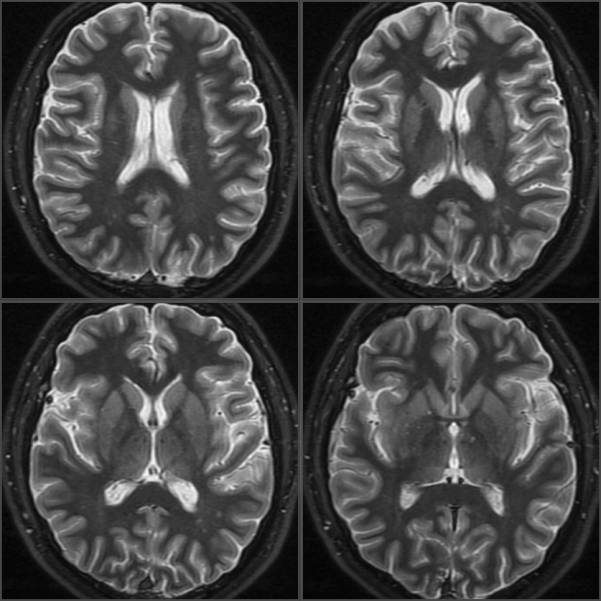

Follow-up MRI

(2013) revealed indirect signs of intracranial hypertension: enlarged perioptic

subarachnoid spaces without cerebral cavity expansion; there were no signs of

brain atrophy. Within the white matter of the brain (posterior watershed zone),

both on the right and on the left sides (Fig. 1, 2), T2 / FLAIR hyperintense

small foci, located in the juxtacortical, subcortical and deep white matter

areas (the border zone) have been found; another similar focus has been visualized

juxtacortical in the front insular region on the left. The foci were rounded or

spindle-shaped with the radial type of location perpendicular to the boundaries

of the lateral ventricles. There were no signs of pathological accumulation of

gadolinium - containing contrast agent after its administration. The number of

foci as well as their sizes and shapes did not undergo any significant

transformation. Due to cumulative signs the referred foci probably belong to

the perivascular domain, suggesting infectious / inflammatory etiology for

these lesions [3].

Fig. 2

Supratentorial axial T2 irFSE - weighted, slice thickness 4 mm.